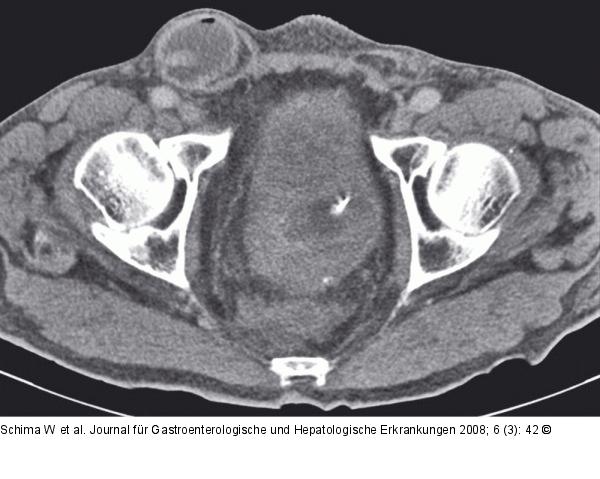

Abbildung 1b-c: Dünndarmschlinge Die MDCT-Bilder im Unterbauch zeigen eine Inguinalhernie rechts mit Prolaps einer Dünndarmschlinge. Die abführende Schlinge ist kollabiert (Pfeil). |

Die MDCT-Bilder im Unterbauch zeigen eine Inguinalhernie rechts mit Prolaps einer Dünndarmschlinge. Die abführende Schlinge ist kollabiert (Pfeil). |